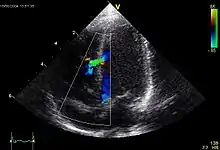

ASD II:

Das heruntergewachsene Septum primum reisst normalerweise in der Mitte ein und bildet das Foramen secundum bzw. Foramen ovale. Dieses wird durch das links vom Septum primum ebenfalls von oben herunterwachsende Septum secundum gardinenartig bedeckt (Ventil) und kurz nach der Geburt durch Umkehr der Druckverhältnisse funktionell (z.T. strukturell durch Verklebung) verschlossen. Ist der Verschluss so ungenügend, dass es zum Links-rechts-Shunt kommt, spricht man vom offenen Foramen ovale bzw. ASD II. Der ASD II ist im Ggs. zum ASD I weiter oben lokalisiert. Er macht oft wenig Symptome und wird oft erst im Erwachsenenalter erkannt. Der Links-Rechts-Shunt kann im EKG zu Zeichen der Rechtsherzbelastung führen (Rechtslagetyp, P pulmonale, inkompletter Rechtsschenkelblock ohne Hypertrophie-Zeichen (rsr's') als Zeichen der rechtsventrikulären Volumenbelastung) und bei starker Ausprägung zu klinischen Symptomen führen.

![]() Echokardiogramm eines VSD. |